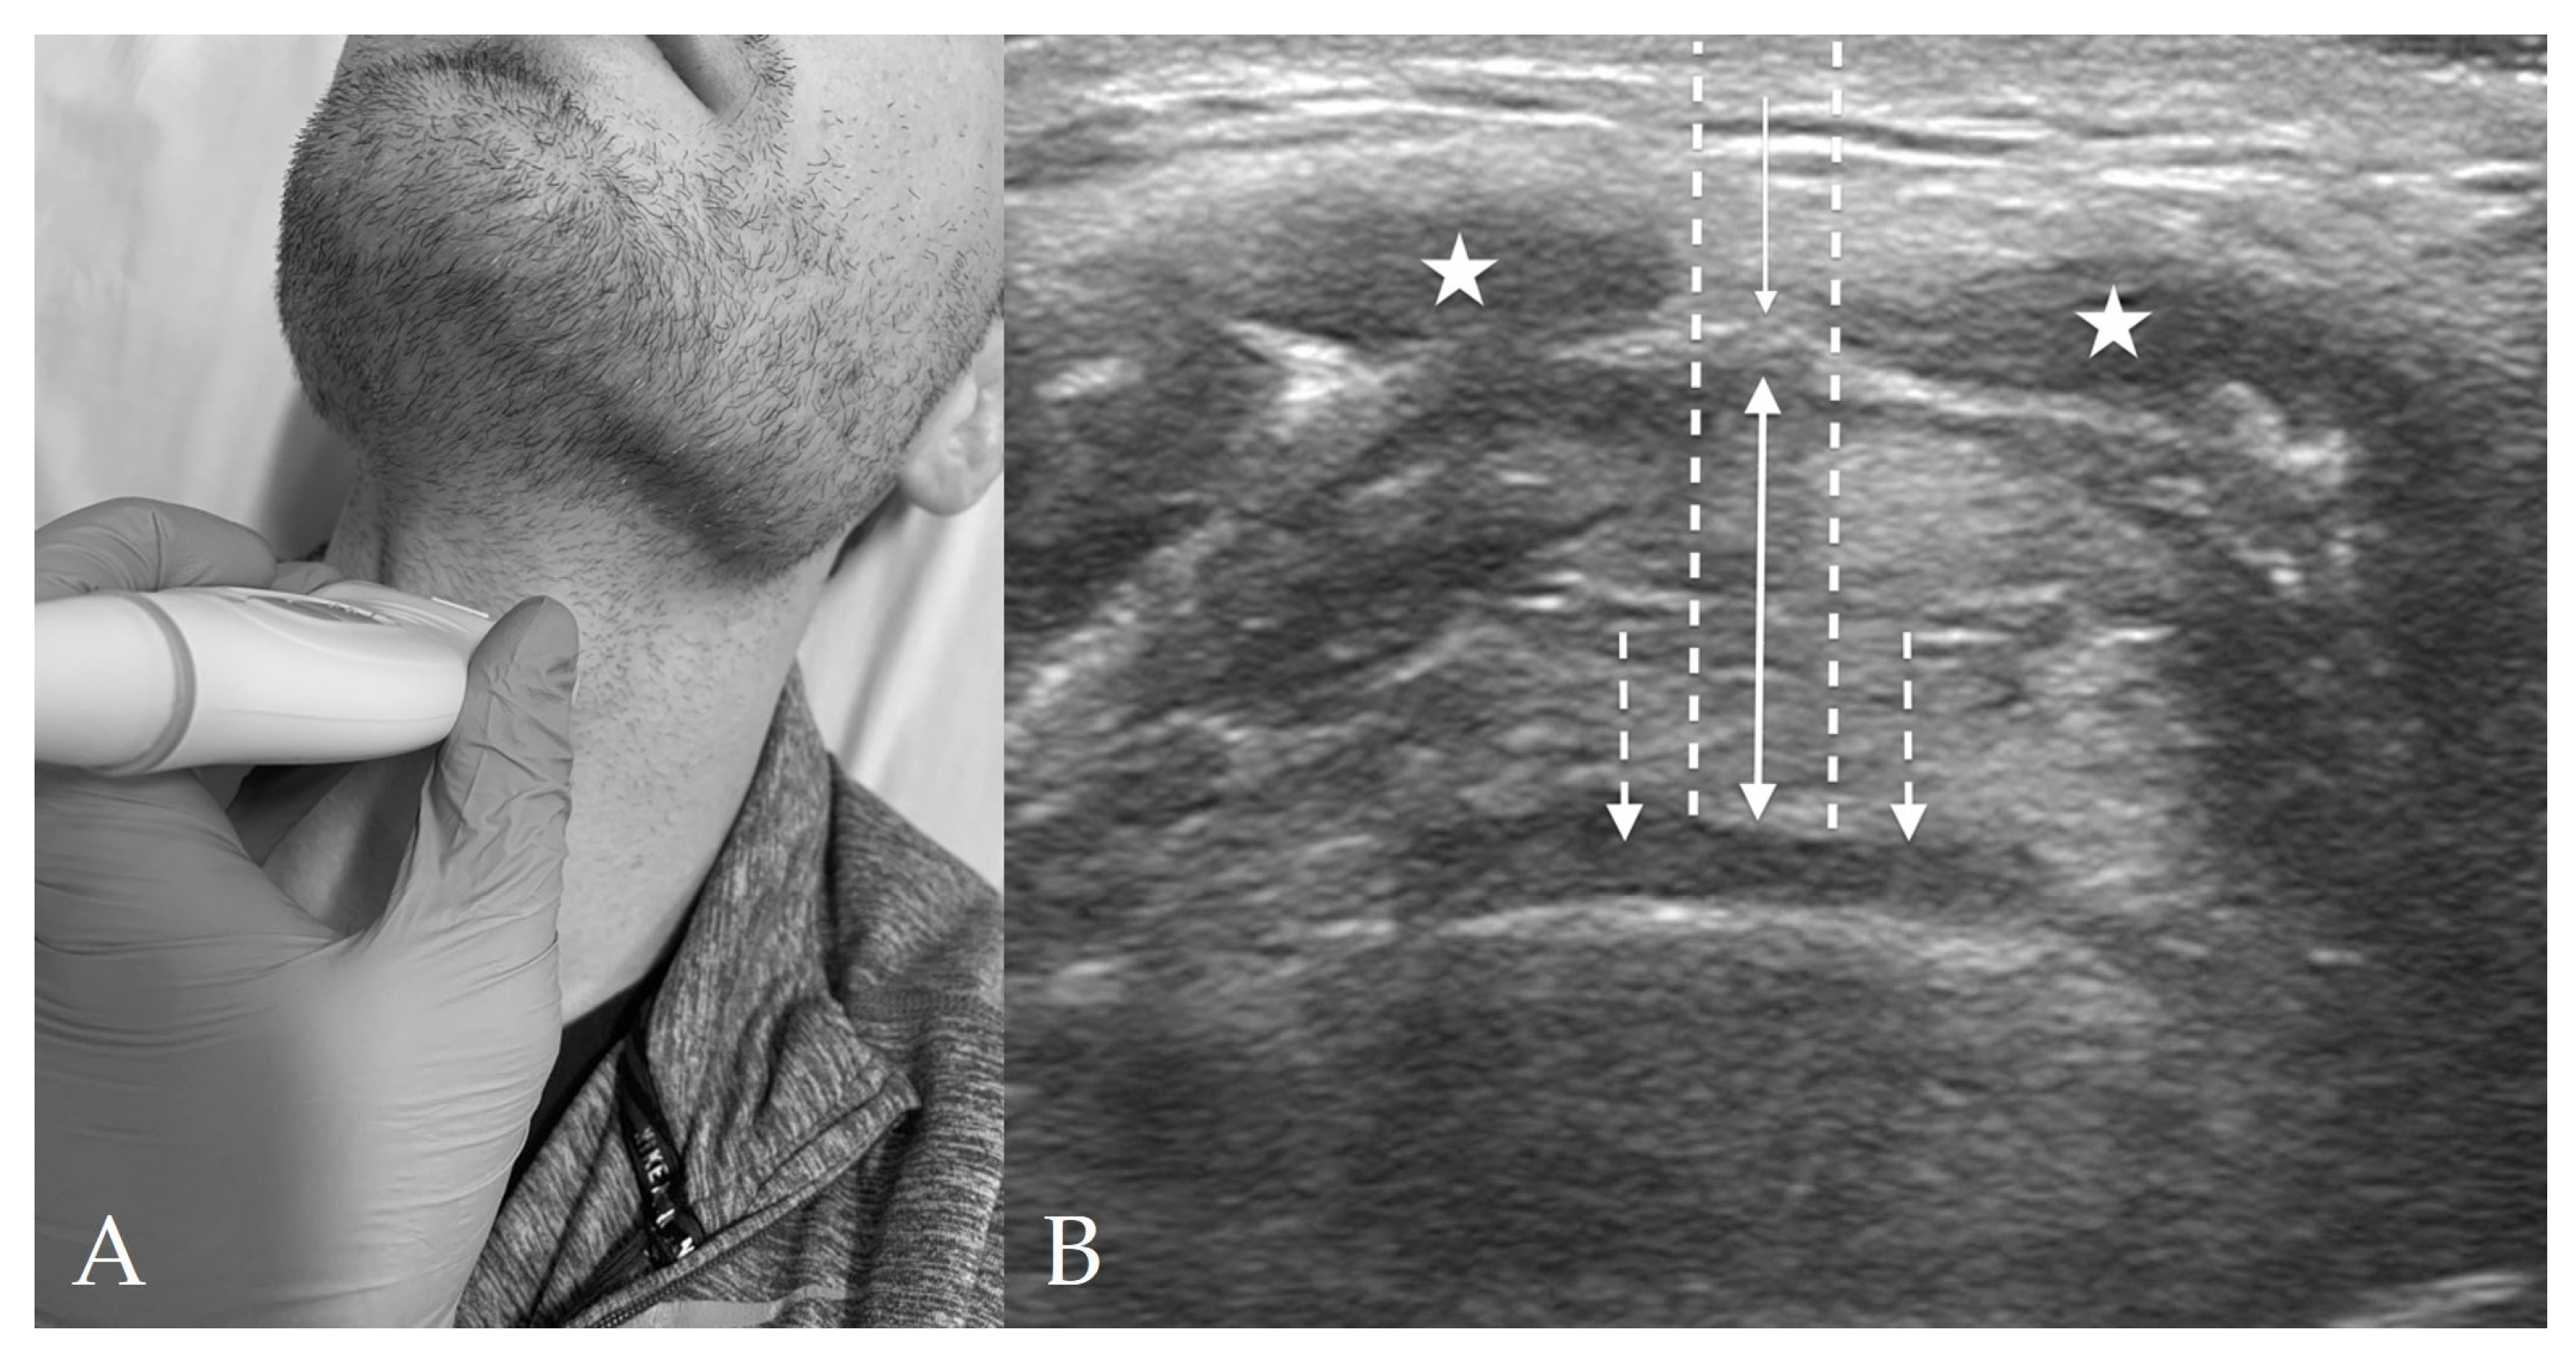

4.2. Thyrohyoid View